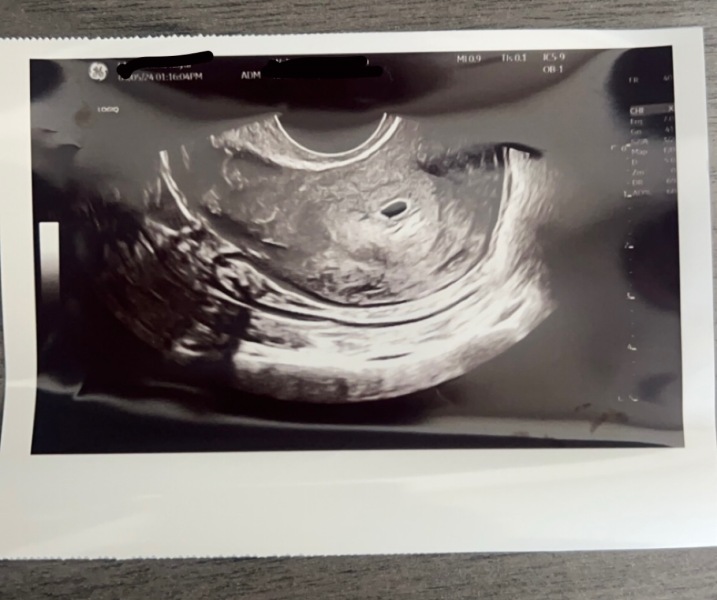

Girlmom2009 · 09/05/2024 14:18

@Marie1990x @TigerMummax3 just had the scan will post a update! I’m still holding out you get your BFP! I have a good feeling 🤍

Scan update 🙏 seen a sac today and just had 5 weeks, nothing else visiable! So that puts my guesses right at 4wks 5 days ish! To re scan in 10 days and again after that. Least we are further then last week when nothing was visable. What do you guys think ?

@Girlmom2009 that’s great news!!! I knew it would be fine considering your test progression. Has it given you some peace of mind? Are you going to tell your partner now?

@Marie1990x it’s given me some hope, but need to see something in there. Todays been rubbish, I’m self employed and lost one of my main incomes so I’m going to try wait until my next scan in 10 days. Not out of the woods yet 🙈I have bad cramps and no from future it’s too early!

@Girlmom2009 yeah completely get you. I think what you saw is normal for your gestation though isn’t it? I didn’t have one that early, but had one at 7w3d and was still only a tiny dot and not much else.